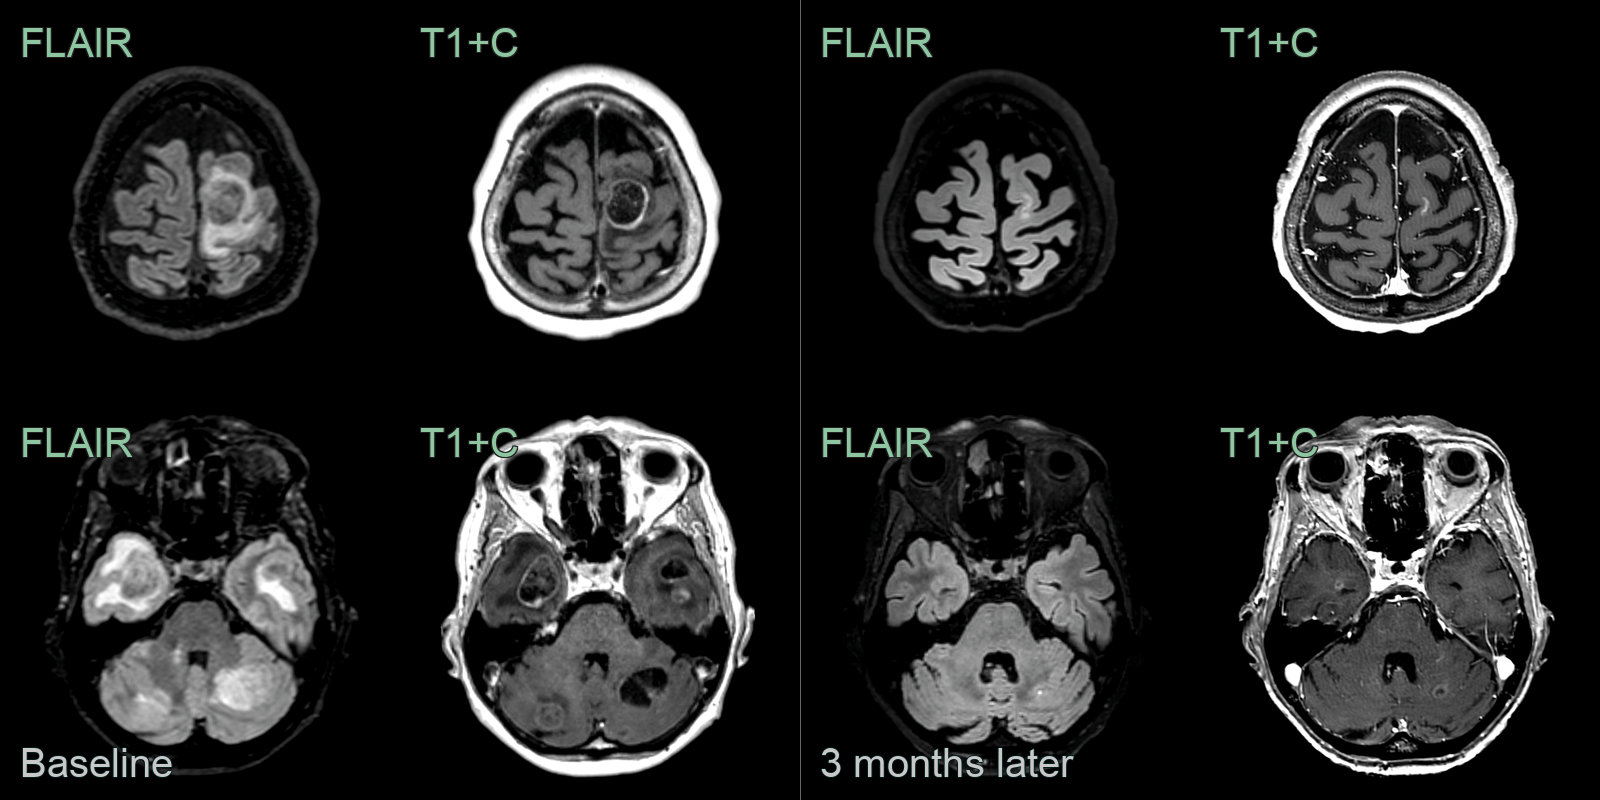

- A 70-year-old patient with small cell lung cancer presented with right leg weakness.

- MRI showed many peripherally enhancing lesions, the larges of which was in the left paracentral lobule.

- Following chemotherapy, MRI showed a marked reduction in the size of all of the lesions and the surrounding edema.